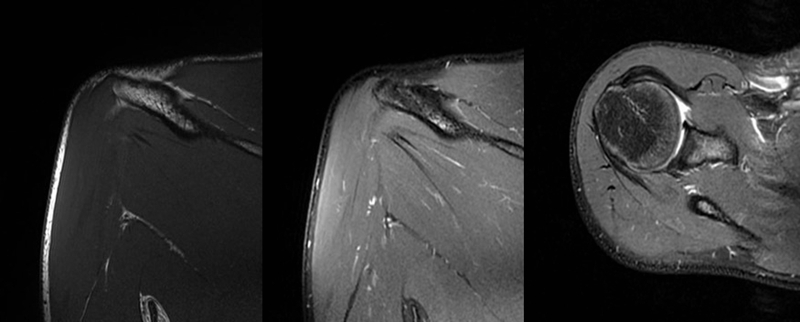

2、MRI检查

MRI目前是诊断肩袖疾病中最常用的检查,可以直观的观察肩袖肌腱。

图19 肩胛下肌

图20 小圆肌

图23 横断位a.正常肩胛下肌;b.肩胛下肌损伤

图24 a.肩袖全层撕裂;b.正常MRI

图25 巨大肩袖损伤(冈上肌)